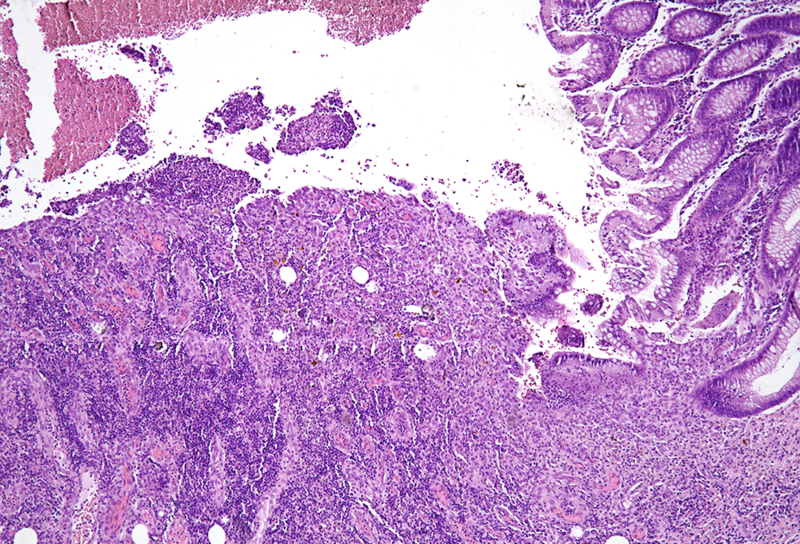

On macroscopy, multiple ulcers were visible on the mucosa of the colon. Histology showed ulcers with prominent granulation tissue, reaching the muscular wall of the bowel. They were surrounded by colonic mucosa with regenerative architectural changes (Panels A-B). In the ulcers and on the surface mucosa, yellow-pink polygonal foreign material with scale-like appearance was seen, which corresponded to the given sevelamer drug (Panels C-D).